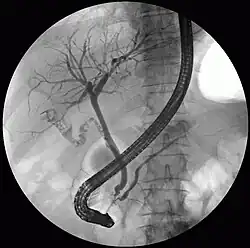

ERCP: Unauffälliger Gallen- und Pankreasgang, mehrere unterschiedlich große Gallensteine in der Gallenblase und im Gallenblasengang

Mit einem durch den Mund (oral) eingeführten Endoskop mit Seitblickoptik, dem Duodenoskop, wird das Duodenum aufgesucht und die Vatersche Papille sondiert, die Mündung des gemeinsamen Ausführungsganges von Gallengang und Bauchspeicheldrüsengang. Das Kontrastmittel wird retrograd, also entgegen der normalen Flussrichtung der Gallenflüssigkeit, in die Gallenwege injiziert. Unter der Durchleuchtung mit Röntgenstrahlen werden Verengungen der Gänge, etwa durch Gallensteine, Gallengrieß oder Tumore, beurteilbar.